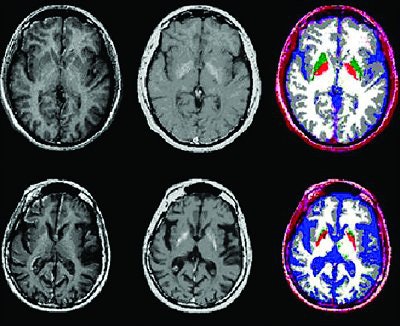

| Axial MR images from healthy subject (top row) and patient with symptomatic Huntington's disease (bottom row). Note smaller fGM and fWM volumes in patient with Huntington's compared to healthy subject. Slices represent R1 and R2 relaxation rates and corresponding segmented images. Segmented images are coded gray for GM, white for WM, blue for CSF, green for putamen, and bright red for globus pallidus. |